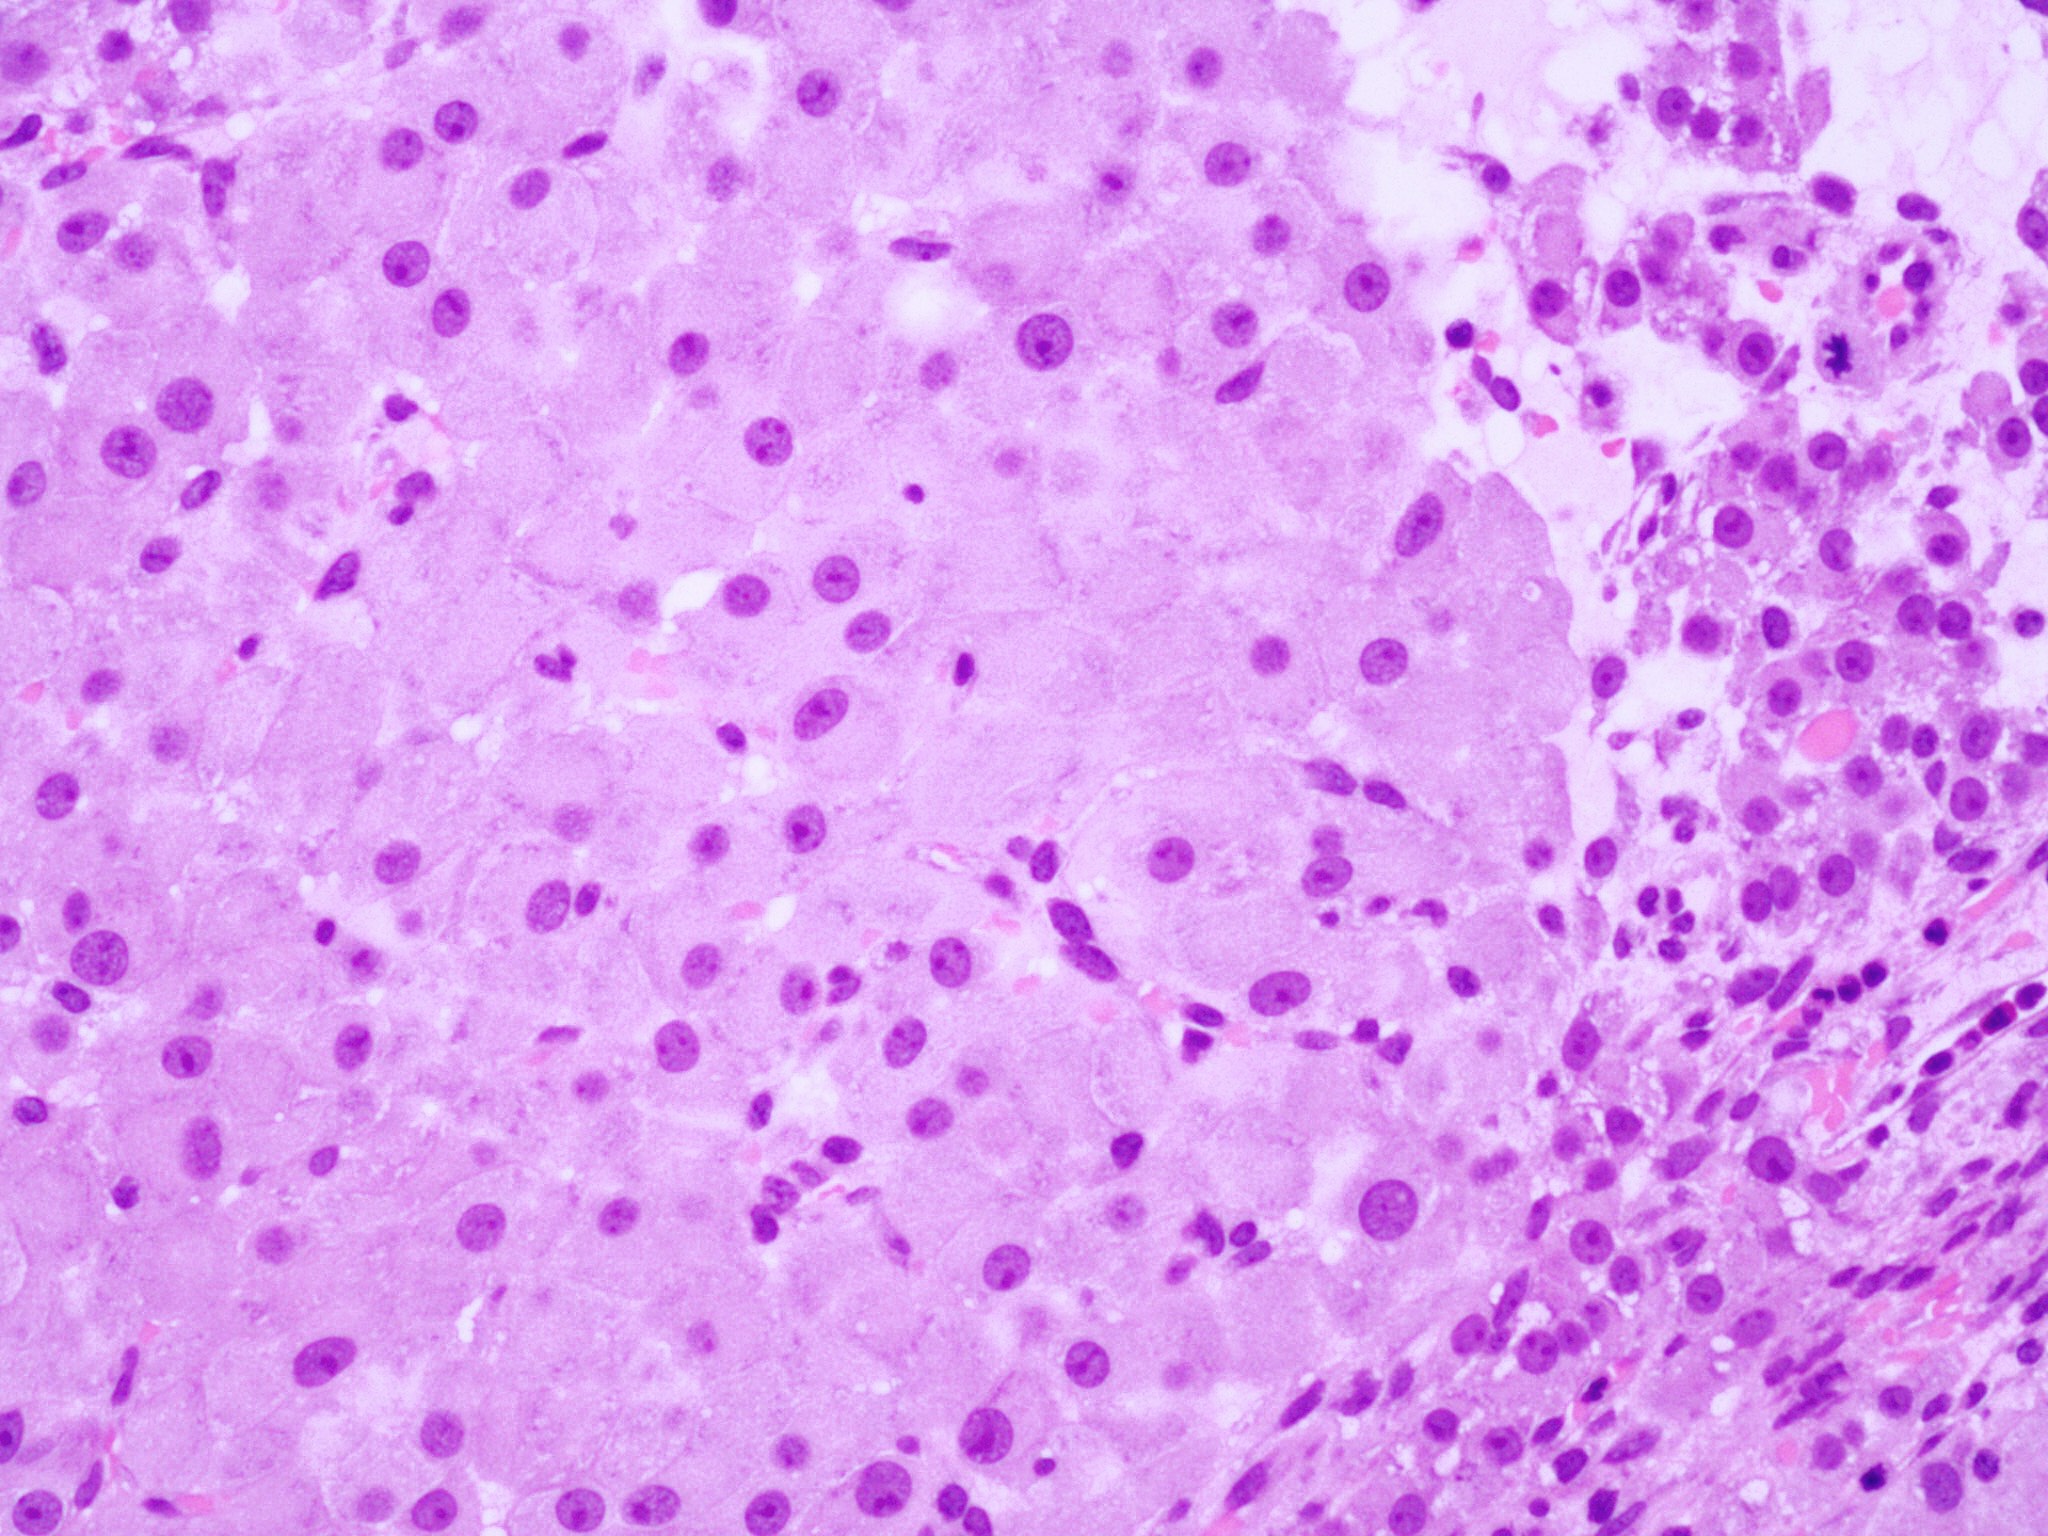

Microscopic (histologic) description

- Cyst lining is convoluted, composed of an inner layer of luteinized granulosa cells and outer layer of theca cells

- Granulosa cells are polygonal in shape, with abundant eosinophilic cytoplasm and central round nuclei

- Mitotic figures may be seen in the granulosa cells

- Outer theca cells are smaller in size

- Prominent inner layer of fibrous tissue

- Reference: Kurman: Blaustein's Pathology of the Female Genital Tract, 7th Edition, 2019

Microscopic (histologic) images